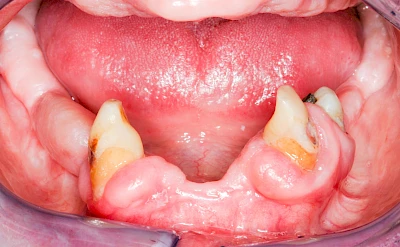

Diese Vermehrung von Bindegewebe in einem frei gewordenen Raum ist eine Sonderform der Anpassungsreaktion menschlicher Zellen und wird als Vakatwucherung bezeichnet.

Früher wurden im Unterkiefer mitunter Brücken zum Ersatz fehlender Zähne als sogenannte "Schwebebrücken" gestaltet. Die Idee dabei war, dass man die Brücke insgesamt besser reinigen kann. Allerdings war das für die Patienten mitunter irritierend für die Zunge und vor allem beim Essen gewöhnungsbedürftig. Teilweise haben sich hier reaktiv Vakatwucherungen der Kieferkammschleimhaut gebildet und den Raum unter der Brücke wieder verschlossen.